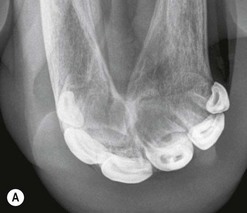

image image image

Fig. 13.36 Polydontia. Supernumerary maxillary cheek teeth (Triadan12s) are the most common supernumerary cheek teeth in horses. The 12 is usually markedly overgrown as in (A) but may be unerupted as in (B) if there is inadequate space (overcrowding). Note the abnormal shape of the apical area of the 112. (C) An example of overgrown bilateral supernumerary mandibular 12s.